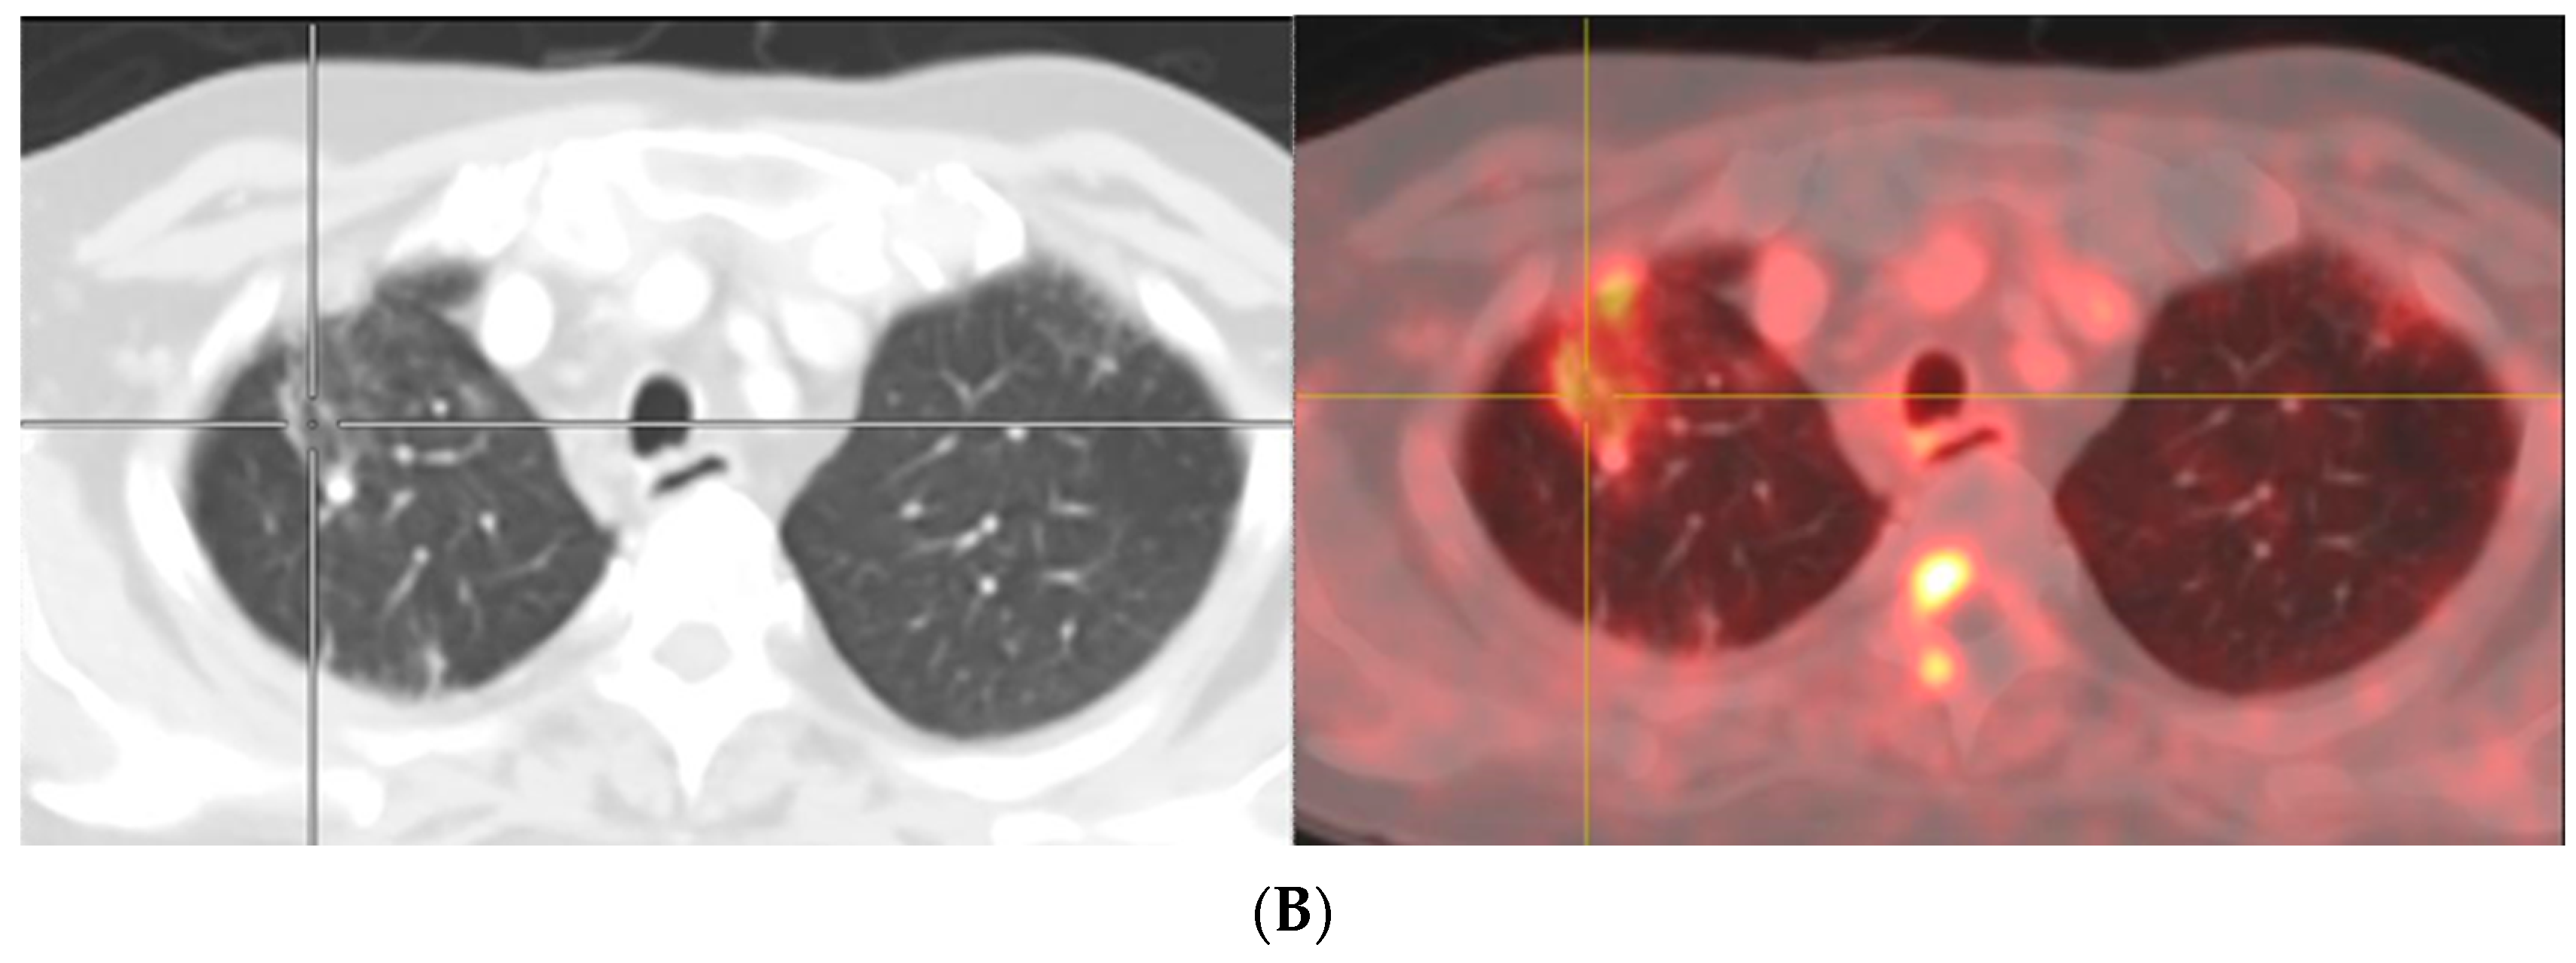

Figure 2.

A 74-year-old man with adenocarcinoma of prostate gland (Gleason score 5 + 4 = 9) S/P radical prostatectomy with bilateral orchidectomy, developed rising serum PSA with level of 1.2 ng/mL which was suspected of BCR. His bone scan revealed equivocal lesions at left scapula, T8, and 12 vertebrae (A). He also performed 18F-PSMA PET/CT for evaluating BCR. There are multiple PSMA-avid lesions on MIP image (B) associated with multiple PSMA-avid mixed osteolytic and blastic metastases at multiple levels of vertebrae, both scapulae and multiple bilateral ribs as seen on coronal PET (C) and sagittal PET (D) images.